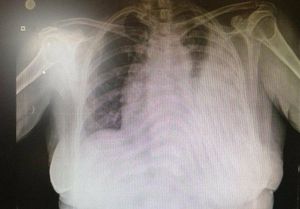

Asymptomatic pleural effusion with negative cytology

Tuberculosis

Tb